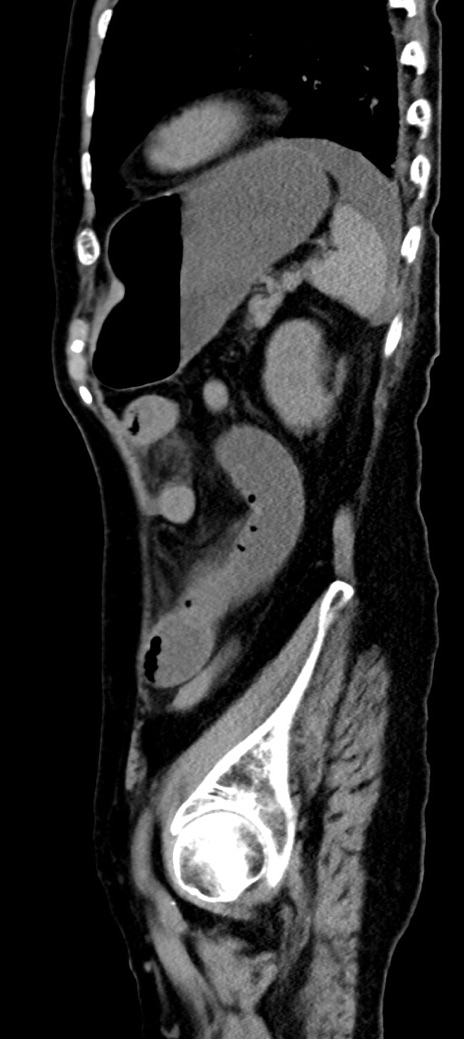

他院CT

横断像

冠状断像